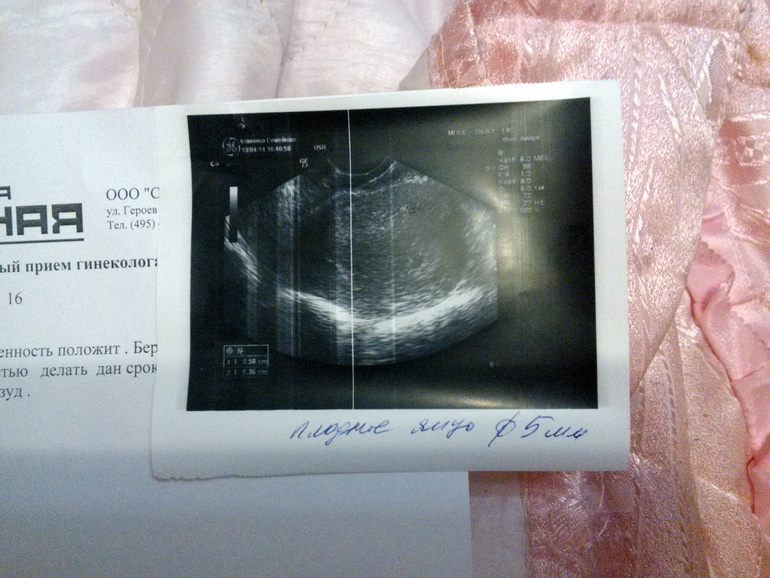

Я очень счастлива:-)Задержка 8 дней решила сделать тест,сделала 7 тестов все положительные:-)Пошла сегодня к врачу,4 недели.На узи увидела маленькое зернышко размер 0,5 мм.Очень счастлива,но страшно.Боюсь рожать.